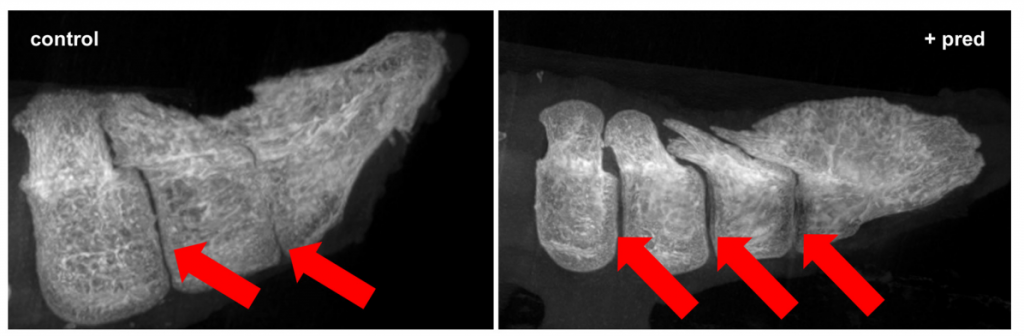

3. การยืดกระดูกหาง (ก้าวสำคัญล่าสุดในปี 2023-2024): การสร้างหางยาวคือความท้าทายที่สุดของโครงการ เพราะนกมีกระดูกหางที่หดสั้นและหลอมรวมกันเรียกว่า “ไพโกสไตล์” (Pygostyle) แต่งานวิจัยล่าสุดในวารสาร PNAS โดยทีมของ Dana Rashid และ Jack Horner (2023) ค้นพบว่า กระดูกหางที่หลอมรวมกันเกิดจากกลไก “การอักเสบแบบปลอดเชื้อ” (Sterile Inflammation) และเมื่อนักวิจัยให้ยาต้านการอักเสบในกลุ่มคอร์ติโคสเตียรอยด์ (Prednisolone) ในช่วงสัปดาห์ที่ 3-8 ของตัวอ่อน พบว่าสามารถยับยั้งการหลอมรวมของกระดูกได้สำเร็จ ส่งผลให้หางยืดตัวยาวออกเป็นข้อๆ ได้

เรื่องที่น่าสนใจคือ งานวิจัยเรื่องการยืดหางไก่นี้ ได้รับทุนสนับสนุน 1 ล้านดอลลาร์จาก W. M. Keck Foundation (2024-2025) ร่วมกับ UC San Diego และ Montana State University เพราะกลไกการอักเสบที่ทำให้กระดูกหางไก่ติดกันนั้น คล้ายคลึงกับโรคกระดูกสันหลังอักเสบยึดติด (Ankylosing Spondylitis) ในมนุษย์ ซึ่งอาจนำไปสู่การพัฒนายารักษาโรคกระดูกในอนาคต

– Rashid & Horner (2023): พบว่าหางนกหดสั้นเพราะ “การอักเสบ” จึงใช้ยาแก้แพ้ (Prednisolone) ระงับการอักเสบในตัวอ่อน ทำให้กระดูกหางยืดยาวออกได้สำเร็จ,,